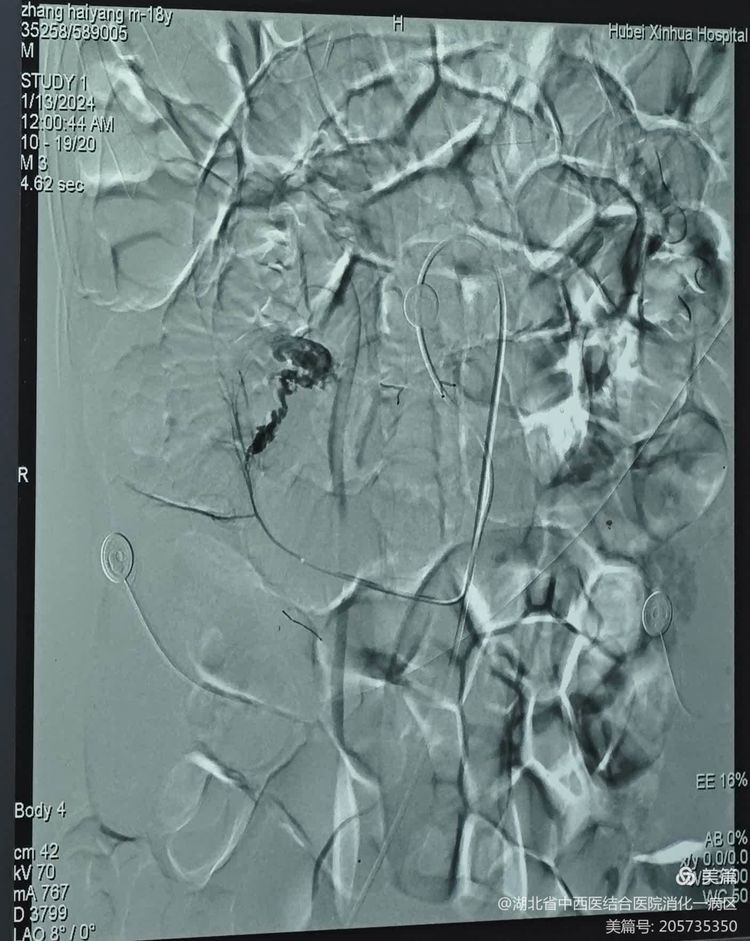

小肠出血的诊断及定位是临床比较棘手问题,为了尽快明确出血部位和原因,挽救患者生命,消化内科一病区屈银宗主任迅速启动了多学科诊疗(MDT),邀请介入科及普外科参与救治。介入科廖凯兵主任迅速赶至医院,带领介入科团队紧急开展腹腔动脉造影术,术中发现肠系上动脉回肠动脉分支“蚯蚓状”血管畸形并可见造影剂明显外溢,考虑小肠出血,出血原因及出血部位已基本明确。经由消化内科、介入科及胃肠外科组成的MDT团队讨论后一致认为该患者有手术指征。当时已是凌晨,胃肠外科沈阳主任医师立即从家中返回医院,带领胃肠外科团队开展急诊手术,因为有了前期胃肠镜及DSA的指引,很快在距回盲部50cm小肠肠壁内发现大小约6*3cm的憩室,憩室内可见大量血凝块,遂立即对病灶进行切除。术后患者病情稳定,未再有便血,复查血红蛋白已升至59g/L,转ICU观察。

急诊腹腔动脉造影术:肠系上动脉回肠动脉分支“蚯蚓状”血管畸形并可见造影剂明显外溢,考虑小肠出血可能。